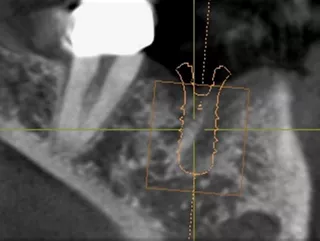

• Planificación digital para establecer una posición del implante basada en la prótesis.